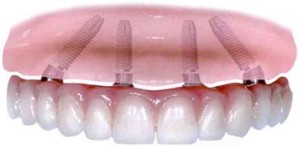

Prosthetic flexibility

With All-on-4, patients benefit from an immediate implant-supported restoration, as a provisional prosthesis is screwed onto the implants right after surgery. Final solutions for All-on-4 include both fixed prostheses, such as NobelProcera Implant Bridge Titanium with acrylic veneering, or individual NobelProcera crowns cemented to the bridge framework, and removable solutions, such as acrylic overdentures on a NobelProcera Implant Bar Overdenture.